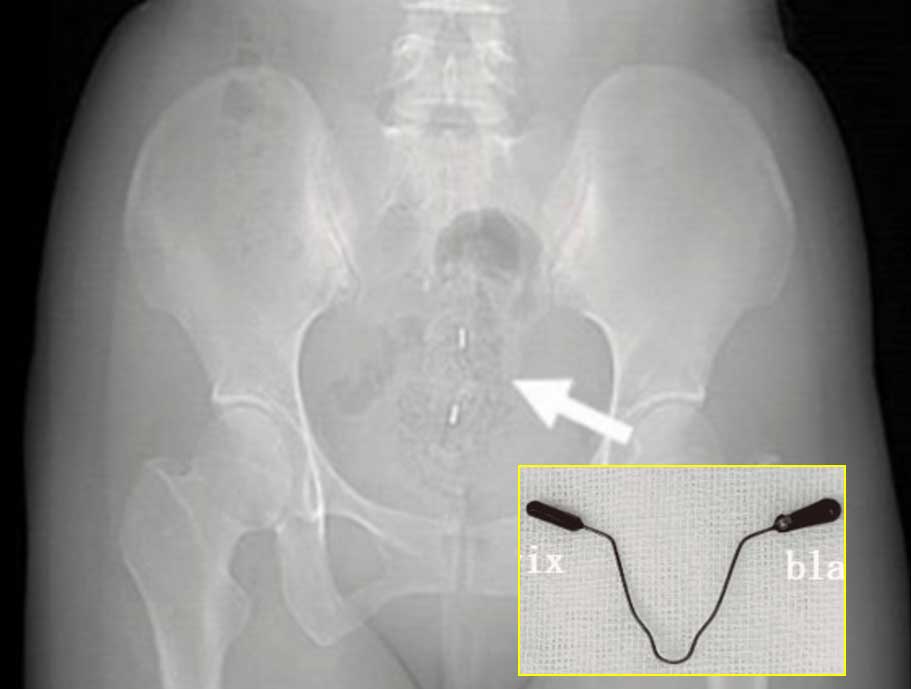

Áß±¹ »êµÕ»êÇöÁß¾Óº´¿ø »êºÎÀΰú ÀÇ·áÁø¿¡ µû¸£¸é, 39¼¼ ¿©¼ºÀÌ 6°³¿ù°£ ºó´¢¿Í ¼º°ü°è Áß ±Ø½ÉÇÑ ÅëÁõÀ» ´À²¸ ³»¿øÇß´Ù. °Ë»ç °á°ú, 2³â Àü »ðÀÔÇÑ ÇÇÀÓ ÀåÄ¡ÀÎ Àڱà ³» ÀåÄ¡°¡ ÀÚ±ÃÀ» °üÅëÇØ ¹æ±¤ Èĺ®±îÁö ÆÄ°íµç »óÅ¿´´Ù.

ÀÇ·áÁøÀº ¹æ±¤À» Àý°³ÇØ Àڱà ³» ÀåÄ¡¸¦ ¾ÈÀüÇÏ°Ô Á¦°ÅÇϰí, ¼Õ»óµÈ ¹æ±¤º®À» ºÀÇÕÇß´Ù. ¼ö¼ú Áß ÃâÇ÷Àº °ÅÀÇ ¾ø¾úÀ¸¸ç Àڱðú ³¼Ò´Â ´ÙÇàÈ÷ Á¤»ó »óÅ¿´´Ù. ¿©¼ºÀº ¼ö¼ú ÈÄ ¿äµµ Ä«Å×Å͸¦ 14Àϰ£ À¯ÁöÇßÀ¸¸ç Á¦°Å ÈÄ ¹è´¢ ±â´ÉÀº Á¤»óÀ¸·Î ȸº¹µÆ´Ù.